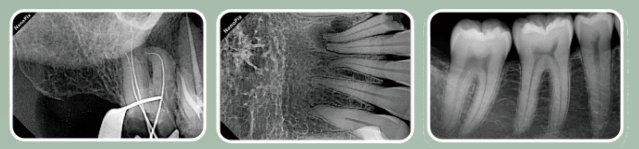

Чёткое изображение с высоким разрешением и фокальным пятном 0.4 мм

• Размытые границы — детектор

• Эффект размера фокального пятна

• Спроектирован для создания точных изображений